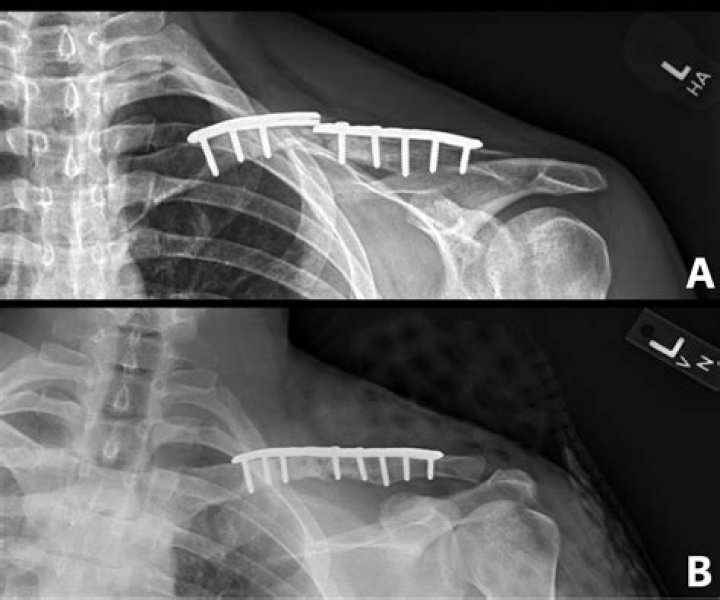

How do you know if a broken collarbone needs surgery?

Specifically, surgery should be strongly considered if the fracture is shortened by 2 centimeters or more, displaced more than 100% (the fractured ends aren’t touching at all), when there are specific fracture patterns (such as Z-type fractures), or when the fractures are highly comminuted (shattered).